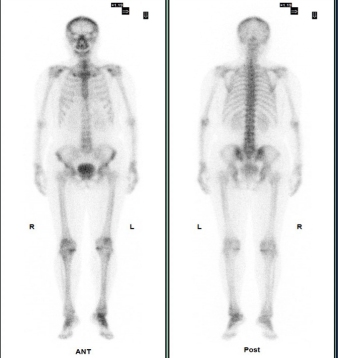

(病例一)患者,男,39岁,右肺门中央型肺癌T3N2MX(IIIB期),为明确是否有骨转移来我科就诊。MIP图示:额骨右侧、C6、T12、左侧第6肋,右侧第7、8肋多发小片状放射性摄取增高灶,SPECT/CT融合图示:额骨右侧、C6、T12、左侧第6肋,右侧第7、8肋未见明显骨质破坏。结合肺癌病史,考虑额骨右侧、C6、T12、左侧第6肋,右侧第7、8肋多发骨转移。如下图: